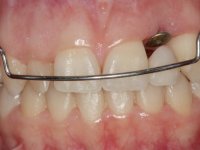

Female patient, 24 years of age, non-smoker. The clinical situation resulted from an orthodontic treatment performed with the intention of resolving a problem of unilateral agenesis of the left lateral incisor. After orthodontic correction, an implant was placed at the site of tooth 2.2. During the period of osseointegration the patient used a removable orthodontic appliance with a prosthetic tooth. Upon assessment of the situation, I registered the following aesthetic conditions:

1. The cervical level of the teeth 1.3.1.2 and 1.1 are at a more incisal level than the teeth 2.1 and 2.3.

2. The distal papillae of 2.1 and mesial of 2.3 disappeared.

3. Slight radicular exposure in distal 2.1 and mesial 2.3.

4. The edentulous space corresponding to the high and narrow 2.2.

5. Tooth 1.2 with microdontia and rolled.